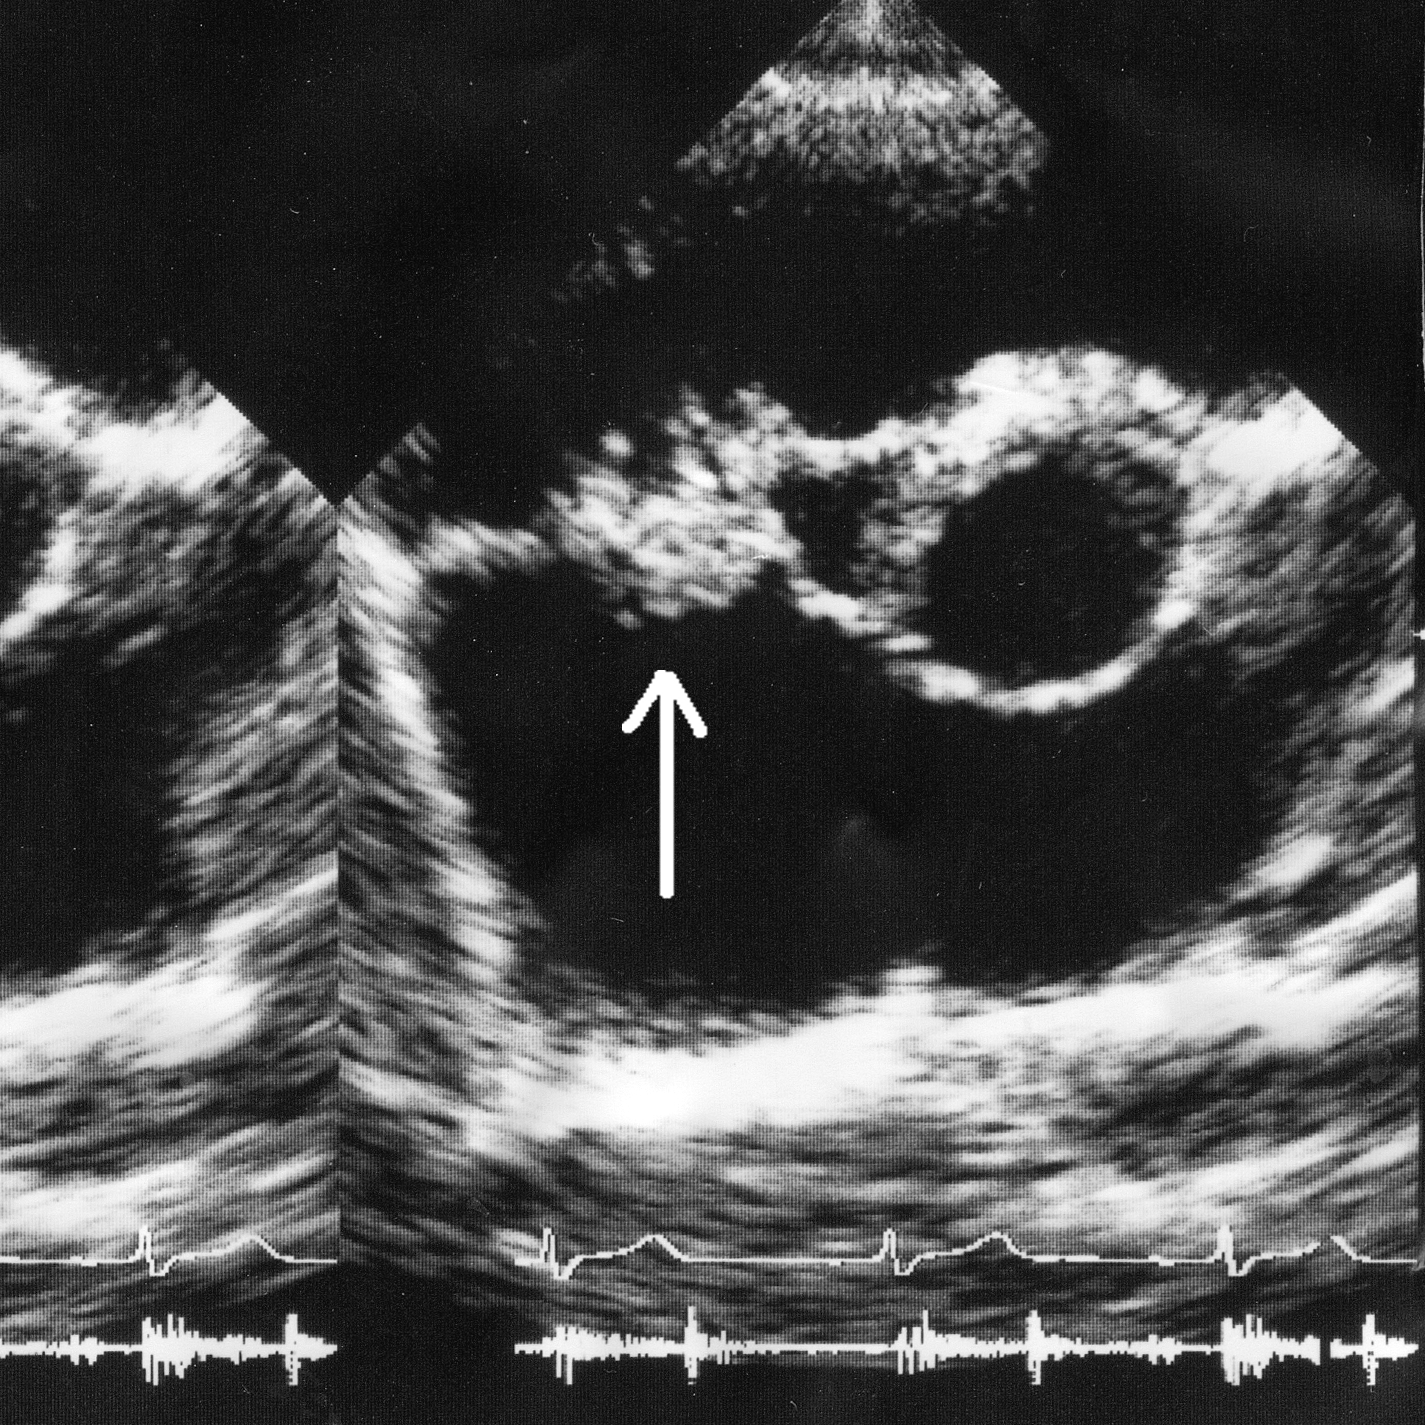

/Join us as we recap a very special week of Grand Rounds here at UCEM! We started off with Dr. David Wright, visiting us from Emory University, to discuss the very latest in ICH management and also share his pearls for developing into leaders in our field. Next, we are joined by Dr. Cheetham, a PEM attending and EMS fellow, who reminds us the importance of EMS handoffs and even offers ways we can improve the safety of our patients. Dr. Martella shares how his previous time spent working in fast food industry helped shape him into the dedicated and compassionate physician he is today. Followed by Dr. Lewis educating each of us on how to better recognize and manage acute-onset pulmonary edema in the crashing patient. Lastly, our PEM colleagues from CCHMC stop by to help us better diagnose and manage a child presenting to ED with a limp. This week certainly highlighted the collaborative nature of our speciality and we are beyond grateful for all our colleagues near & far that help make us into better providers!